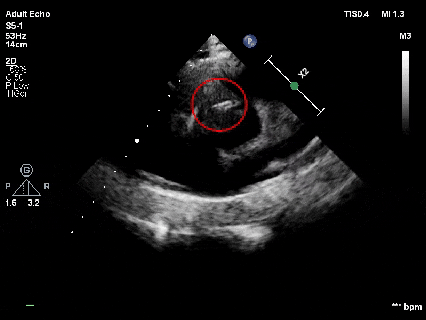

释放前超声

释放前超声下封堵器型态良好,骑跨室间隔两侧

释放封堵器

释放后超声